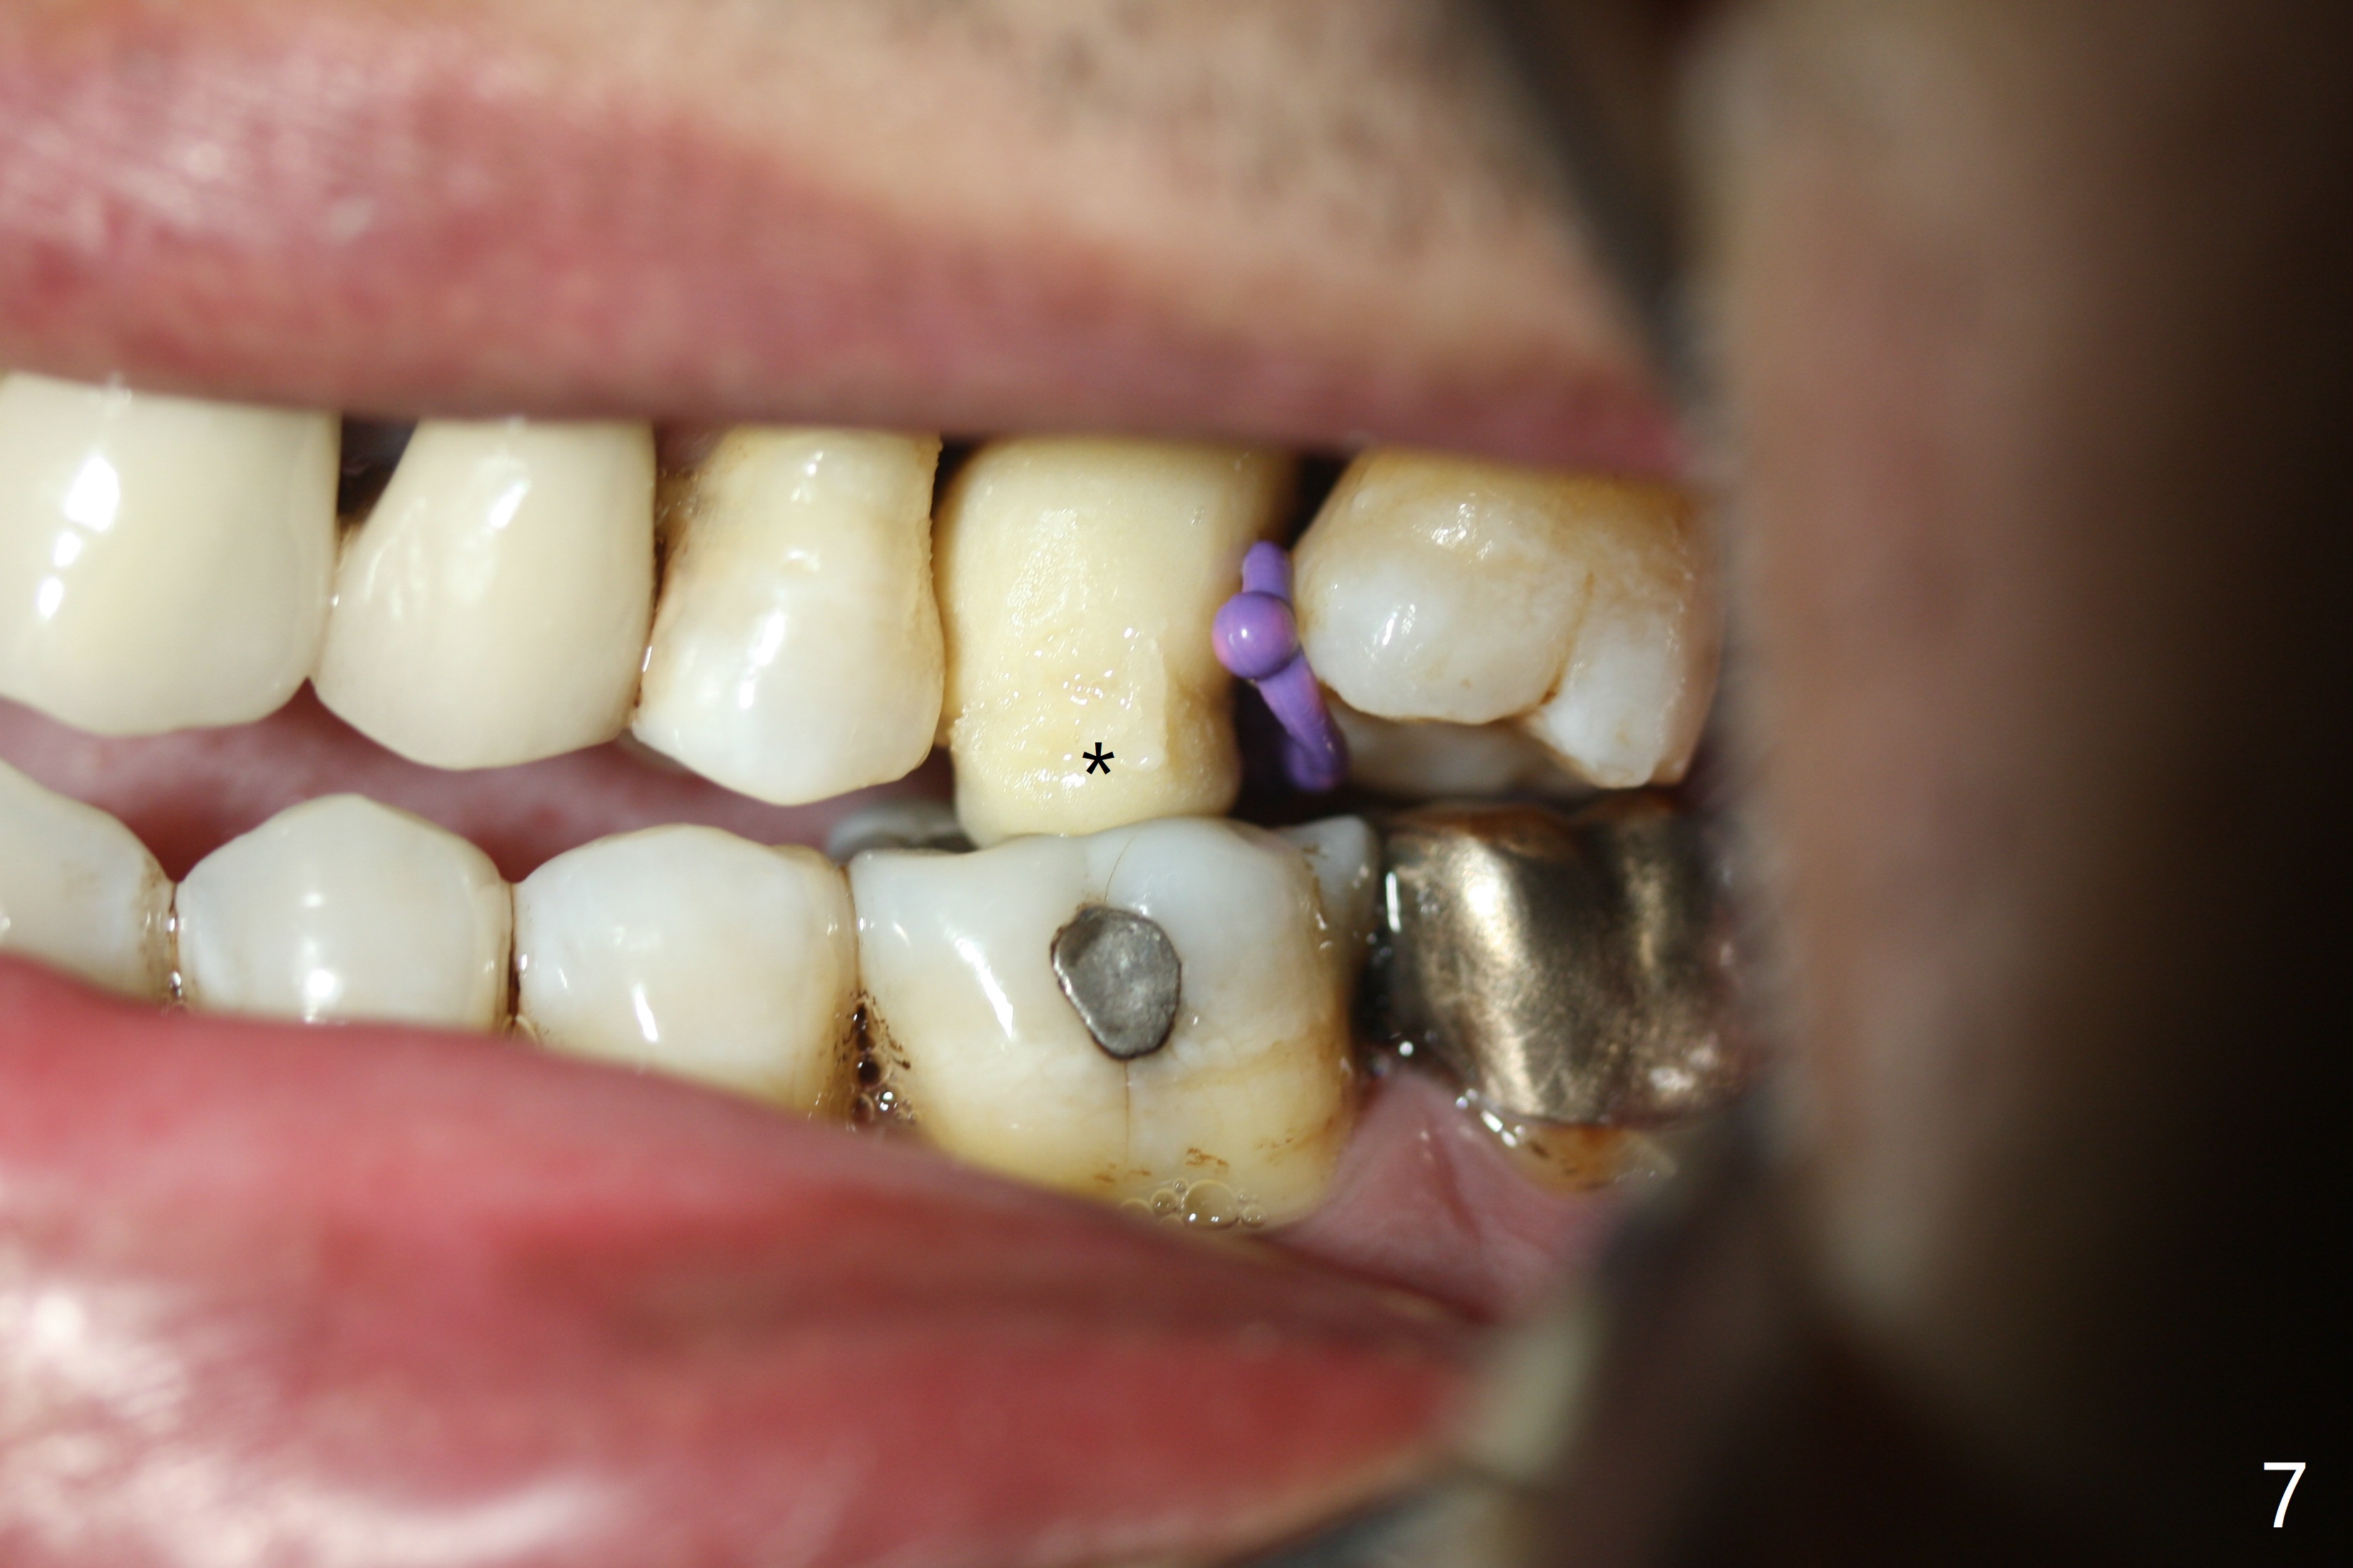

Six months post 2nd placement at #14, the 5x11 mm IBS implant is unstable. The patient smokes a cigarette a day.  After implant removal, the palatal wall of the osteotomy is intact, although low.  With removal of minimal granulation tissue, a 5x10 mm IS dummy implant is placed with stability and slightly subgingival palatal (Fig.1,2).  A 5x8.5 mm definitive implant is placed with ~ 40 Ncm and 3-4 mm subgingival palatal (Fig.3,4).  A 5.7x5.5(5) mm abutment is placed to hold periodontal dressing in place.  If the implant fails again, bone graft should be placed.  The abutment and implant are stable 4.5 months postop (Fig.5); a provisional is fabricated for progressive loading.  The provisional at #14 is narrow mesiodistally, while the tooth #15 is mesially tilted and shifted because of chronic periodontitis and 1 year 4 months of edentulism (Fig.6*).  Limited orthodontics is necessary prior to final restoration.  The 1st step is to raise the occlusion with #14 temporary reline (Fig.7 *); the tooth #15 is distalized initially with a separator, which is inefficient.  It appears that brackets and bands should be placed for distalization.  A month post banding, open coil spring is placed between #14 and 15; with occlusal composite on the opposing tooth (#19) (Fig.8), the tooth #15 is distalized instantly probably related to its periodontal condition (Fig.9 mirror view).  The tooth #15 is further distalized 2 weeks post open coil spring placement (Fig.10).  To act an anchorage, the abutment needs to be torqued with wrench (25-30 Ncm) and the provisional has to be permanently cemented.  The distalization appears to be ~ 1 mm shy 1.5 months post open coil (Fig.11).